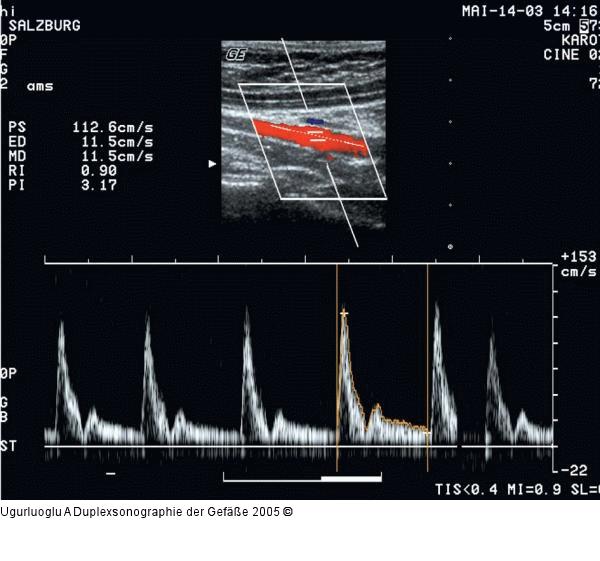

Abbildung 6: Duplexsonographie - A. mesenterica sup. Darstellung der Arteria mesenterica superior im Triplex-Modus, sagittaler Strahlengang. Kontinuierlicher diastolischer Fluß, Vsyst: 112 cm/sec., Vdiast: 11 cm/sec., RI 0,90. |

Darstellung der Arteria mesenterica superior im Triplex-Modus, sagittaler Strahlengang. Kontinuierlicher diastolischer Fluß, Vsyst: 112 cm/sec., Vdiast: 11 cm/sec., RI 0,90. |